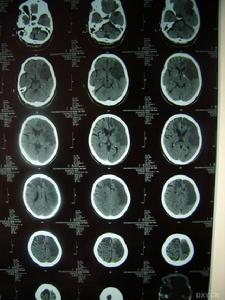

⑥影像學檢查:MRI顯示非典型性腦白質病。可見,腦室周圍多發的梗死灶及白質變性,可累及兩側半球皮層、白質及腦室周圍、基底節、橋腦白質等部位。

影像學檢查示:患者姐弟的CT均可見,但當地的CT顯示欠清楚。患者的頭顱CT可見多發白質變性;MRI清晰可見多發白質變性及小梗死病灶,病灶大小不一,均呈長T1、長T2信號,病灶累及雙側半球、腦室周圍、腦幹、橋腦,小腦未見病灶;梗死灶分布在底節區,MRA(血管的磁共振影像)顯示顱內血管正常。